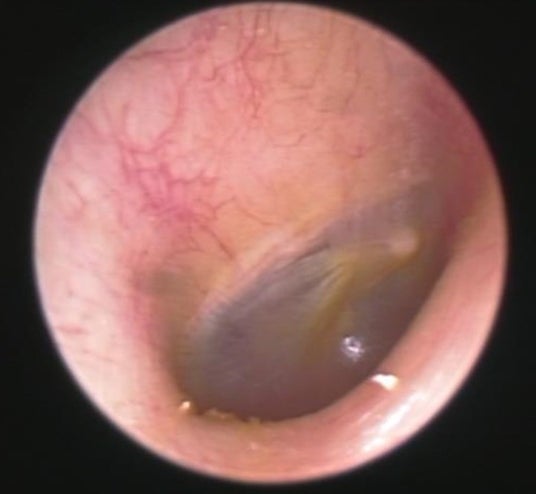

正常な耳:提供そらいろ耳鼻咽喉科センター北駅前院

■外耳炎、耳掃除が主な原因から、イヤホン使用をきっかけに発症するケース増加

昨今、外耳炎や耳カビなども注目される中、今回のラウンドテーブルでは、そらいろ耳鼻咽喉科センター北駅前院 院長の内尾 紀彦先生より、昨今の患者の傾向やイヤホンで起こる外耳炎や耳のトラブルについてお聞きしました。

『外耳炎は、耳の入り口から鼓膜までの「外耳道」と呼ばれる部分の皮膚に細菌が繁殖しておきる病気です。真菌(カビ)が繁殖すると、外耳道真菌症(耳カビ)になります。発症リスクが上がる原因のひとつとして「密閉型イヤホンの長時間使用」が挙げられます。

主な症状は、かゆみ、痛み、耳が詰まったような感じ、聞こえにくさです。特にかゆみは薬で治療しないとサイクルから抜け出せません。温度が20~30度、湿度が60%以上、風通しが悪く日陰だとこのようなカビが繁殖することがあります。密閉型のイヤホンを長時間装着すると、このようなカビができるリスクが高まります。治療法として、外来でカビを掃除して薬を塗ることを繰り返し行いますが、1ヶ月~数ヶ月かかることも稀ではありません。

耳のトラブルを放置すると、治りにくくなる、聴力が低下する、さらに悪化してしまい中耳や内耳、悪性外耳道炎などの重篤な病気が進行してしまう場合もあります。痒みや違和感は無理せずケアをしましょう。』と医師の観点から解説していただきました。